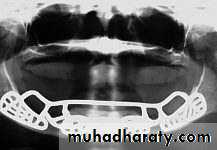

Subperiosteal implant full-arch denture prosthesis.

Sub-periosteal implant

Subperiosteal Implants were already introduced in the 1940s. Of all currently used devices, it is the type of implant that has had the longest period of clinical application. These implants are not anchored inside the bone, such as Endosseous Implants, but are instead shaped to ride on the residual bony ridge of either the upper or lower jaw. They are usually not considered to be osseointegrated implants.Subperiosteal Implants have been used in completely edentulous as well as partially edentulous upper and lower jaws. However, the best results have been achieved in treatment of the edentulous lower jaw.

Indications:

Usually a severely resorbed, completely edentulous, lower jaw bone which does not offer enough bone height to accommodate root form Implants as anchoring devices.4-Transosteal Implants